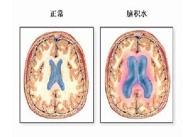

高原腦水腫癥狀

• 高原腦水腫

628健康網為您分享有關高原腦水腫的癥狀,高原腦水腫的治療方法,高原腦水腫的預防知識,高原腦水腫的癥狀圖片,高原腦水腫...